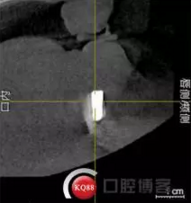

檢查:上頜無(wú)牙頜假牙穩(wěn)定性尚可,下頜3435364243殘根;33殘冠1-2度松動(dòng),其他牙齒缺失;CBCT檢查:下頜牙槽骨前牙區(qū)骨高度足,后牙區(qū)骨高度最低為8mm,骨寬度足。

2)術(shù)前準(zhǔn)備及手術(shù)過(guò)程,測(cè)量血壓及血糖,簽種植知情同意書;嚴(yán)格遵循無(wú)菌操作,局麻下采用微創(chuàng)技術(shù)于323436分別植入osstem4.0X10,4.0X10,4.5X7; 434446分別植入osstem4.0X1O,4.0X10,4.5X7.初期穩(wěn)定性均達(dá)到了35N.CM以上;嚴(yán)密縫合,止血,種植體位點(diǎn)和方向與設(shè)計(jì)一致。